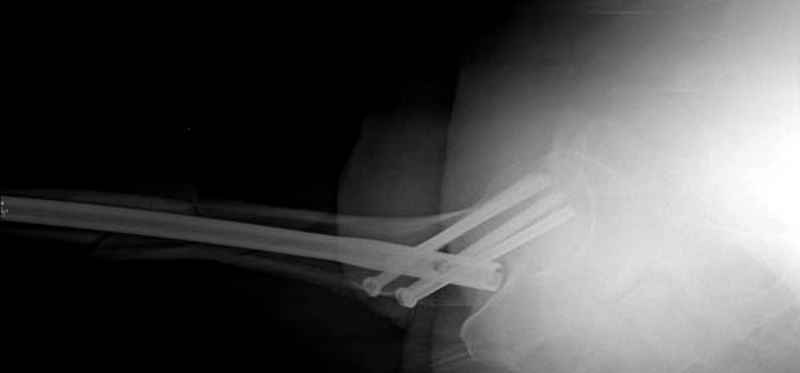

Среди русскоговорящих коллег Ортофорум стал одним из мест, где многие из нас черпают знания для решения своих ежедневных проблем в виде практических советов и обмена опытом. Кроме таких советов, Ортофорум стал источником новых познаний среди ортопедов, особенно по редко встречающимся состояниям в ортопедии. Продолжая традицию, я хотел бы представить редко встречающий случай перелома бедра у больного с гемофилией. Больному 42, гемофилия типа А, из истории упал с высоты около 1,5 метра, переправлен из другой больницы. По происхождению мексиканец, 10 лет назад по поводу артроза пр. коленного сустава в Мексике сделано протезирование, которое закончилось ампутацией выше коленного сустава. При поступлении бедро напряженное, сосудистых и неврологических расстройств нет. На рентгенограмме оскольчатый перелом бедра с вовлечением проксимальной спирали в шейку бедра. Хотели бы знать тактику ведения подобных больных и на что надо обратить внимание? Djoldas Kuldjanov, MD Department of Orthopedic Surgery St. Louis University Medical Center

Учитывая, что случай ургентный, больной поступил вечером, не стали делать вытяжение и срочно провели операцию по фиксации перелома бедра антеградным штифтом Versa Nail от DePuy.

Для профилактики дальнейшего раскола в шейке предварительно во время проксимального рассверливания спереди и сзади провели временные спицы, которые в дальнейшем были заменены на шурупы (miss nail method)